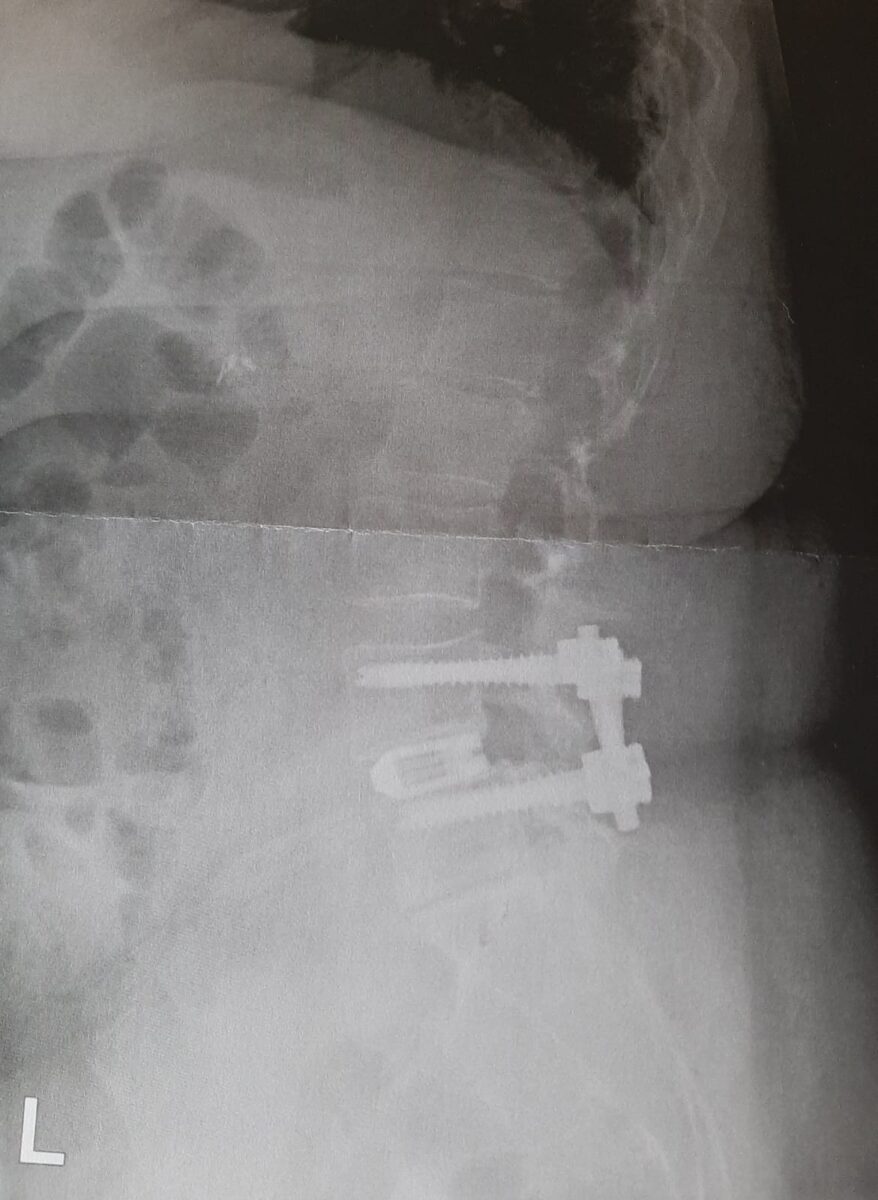

Ik werd ook nog even opgehaald om een röntgen foto te maken, ik had het hartstikke druk die ochtend hahaha

Het staan voor de foto ging gelukkig prima, ik werd niet naar of duizelig. Het scheelt wel dat je je goed vast kan houden en ze echt super geduldig met je zijn. De foto hiernaast is van de zijkant genomen, best gek om dit zo te zien eigenlijk.

rontgenfoto, ziekenhuis

De rontgenfoto, hierop zie je dat de schroeven en het blokje goed zitten.